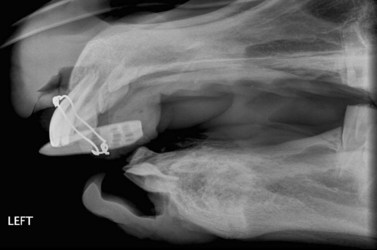

For anesthetized horses, which are usually positioned in lateral recumbency with the affected side uppermost (to allow access for surgery), the cassette is placed beneath the horse’s head, i.e., next to the unaffected side, rather than next to the affected side as is the case for standing horses. Therefore the angle of the X–ray beam must be reversed (compared to the standing horse) to obtain oblique projections of the cheek teeth or sinuses, e.g., for maxillary cheek teeth apices with the affected side uppermost, a ventrolateral to dorsolateral beam direction is required (Fig. 13.10). This projection creates more magnification of the image but should not have a deleterious effect on surgical decision-making unless measurements for surgical implants (e.g., dynamic compression plates) are being made. In such cases, placing a metal marker of known size in the region of interest allows for calculation of the degree of magnification and subsequent correction.

image

Fig. 13.10 Lateral oblique radiographic projections of the maxillary (red arrow) and mandibular (blue arrow) cheek tooth apices in an anesthetized, laterally recumbent horse undergoing surgery. The affected side is placed uppermost to allow surgical access to the lesion (orange circles), and the cassette is placed underneath the head. The X-ray beam must be directed in the opposite direction to conventional views, and more magnification of the image results.